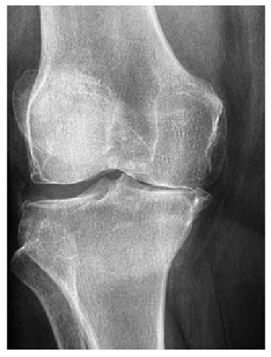

Table 5. X-ray Images.

X-ray 1X-ray 2X-ray 3X-ray 4X-ray 5

Mathematics 10 02421 i004 Mathematics 10 02421 i005 Mathematics 10 02421 i006 Mathematics 10 02421 i007 Mathematics 10 02421 i008

For the purpose of simulation, we consider two sets of images: (1) three images from MATLAB repository (Table 4) and (2) five X-ray images available online (Table 5).